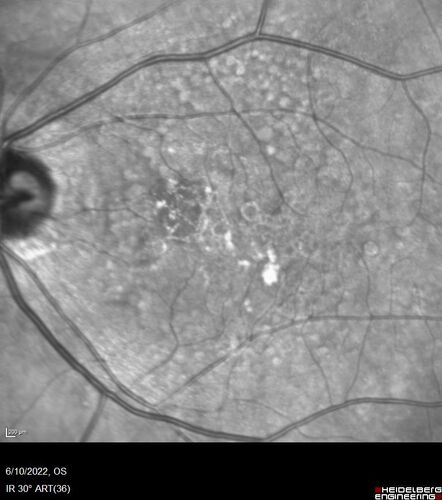

Dry AMD - Pigment - AREDS risk score of 4

65 year old woman with 20/32 vision. A little blurred. Pigment and large drusen in each eye. AREDS risk score of four.